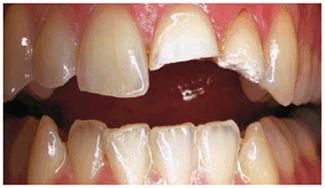

Figur 323s1823d e 18-5A: This 65-year-old man had fractured his right central incisor. Because he desired a younger and brighter looking smile, six porcelain laminates were treatment planned.

Figur 323s1823d e 18-5B: This patient had an end-to-end bite, which required additional incisal edge reinforcement.

Figur 323s1823d e 18-5C: Note the improvement in this man's smile with a lighter shade and teeth that are more proportionate to each other.